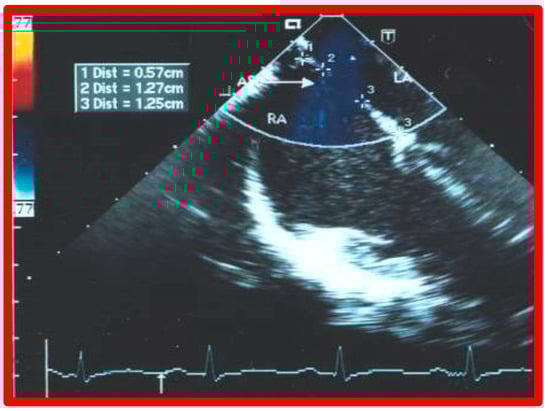

4. Patient Selection for Device Occlusion